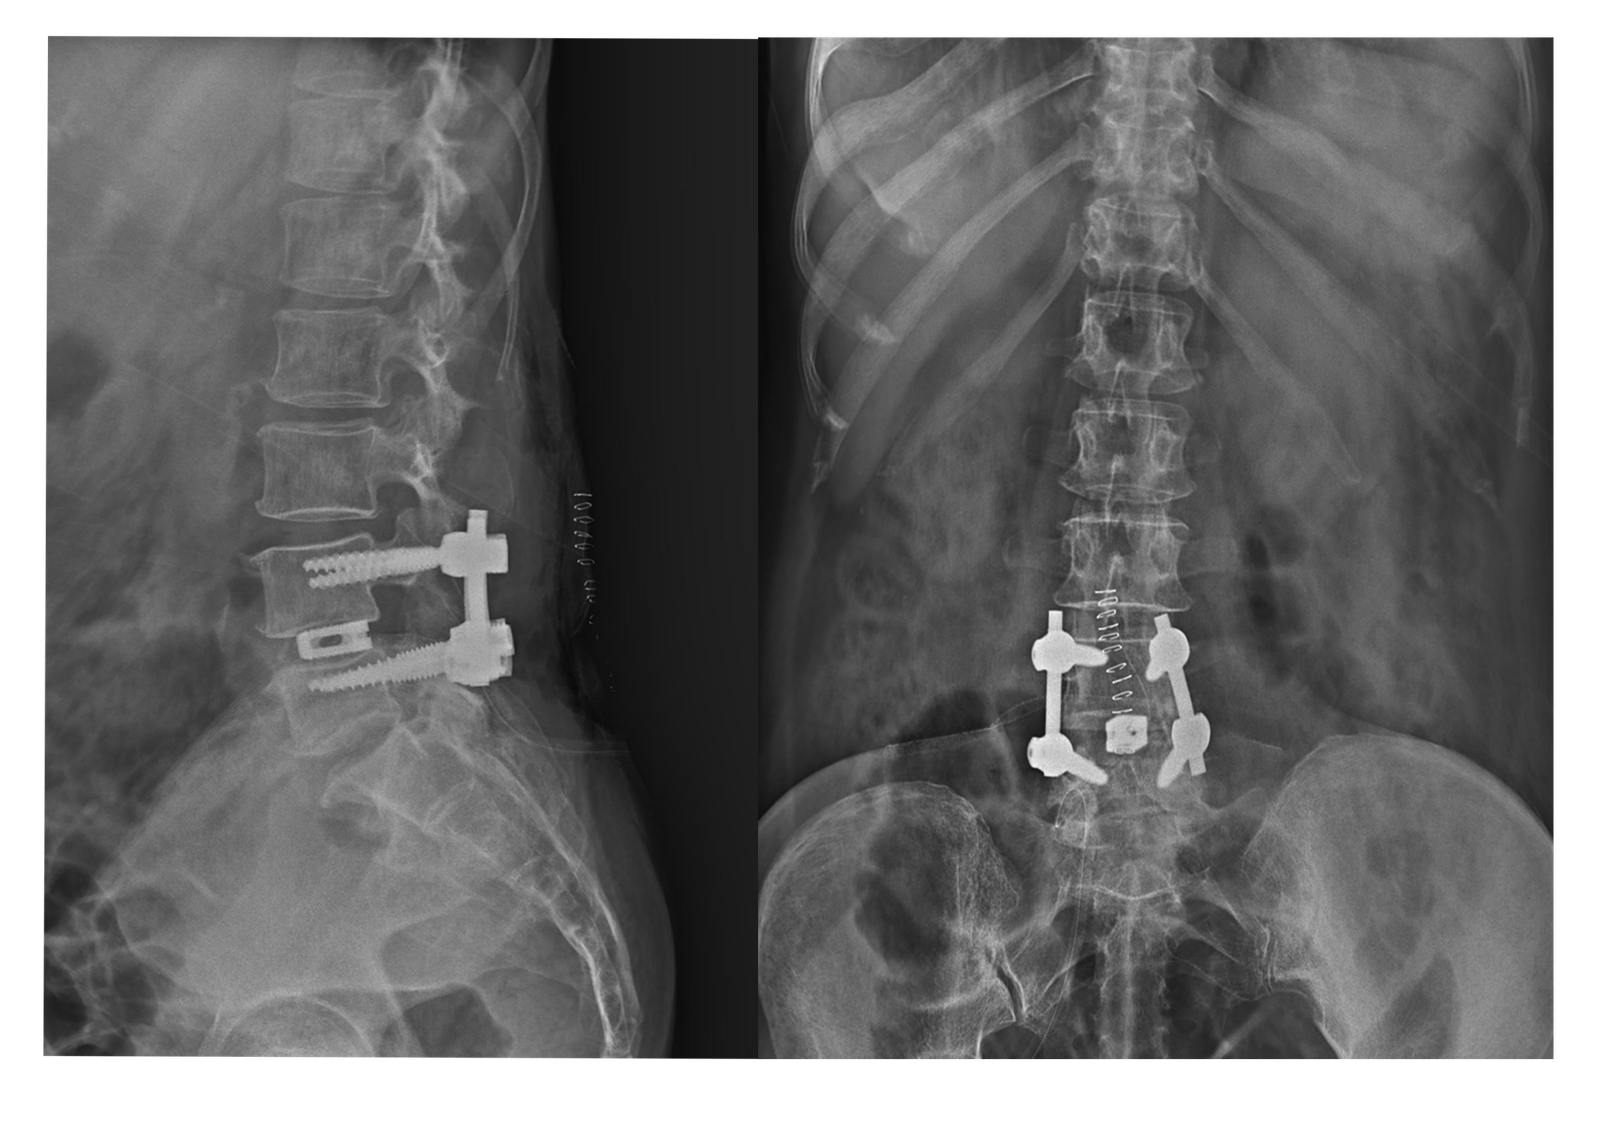

X-Rays